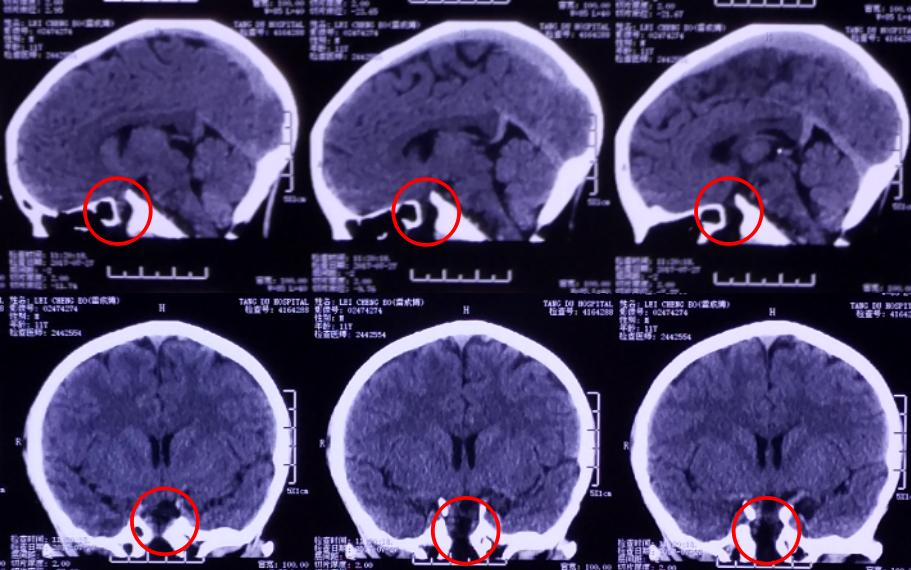

影像资料